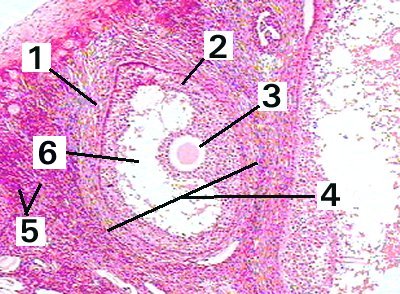

This is a low magnification of a mature ovarian follicle demonstating the different layers and structures.

Fig 89-001 1. Follicular theca

2. Granulosa cells

3. Ovum

4. Ovarian follicle

5. Stroma

6. Follicular antrum